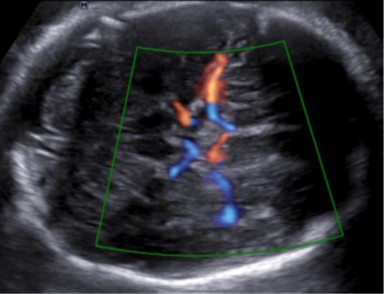

Fetale Neurosonografie